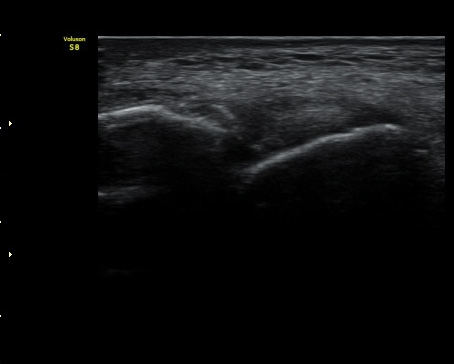

ÃÊÀ½ÆÄ °Ë»ç

ÃÊÀ½ÆÄ °Ë»ç ½Ã ¹ß¸ñ °üÀýÀÇ ¼ö¾×Àú·ù°¡ °üÂûµÊ(±×¸² 1).